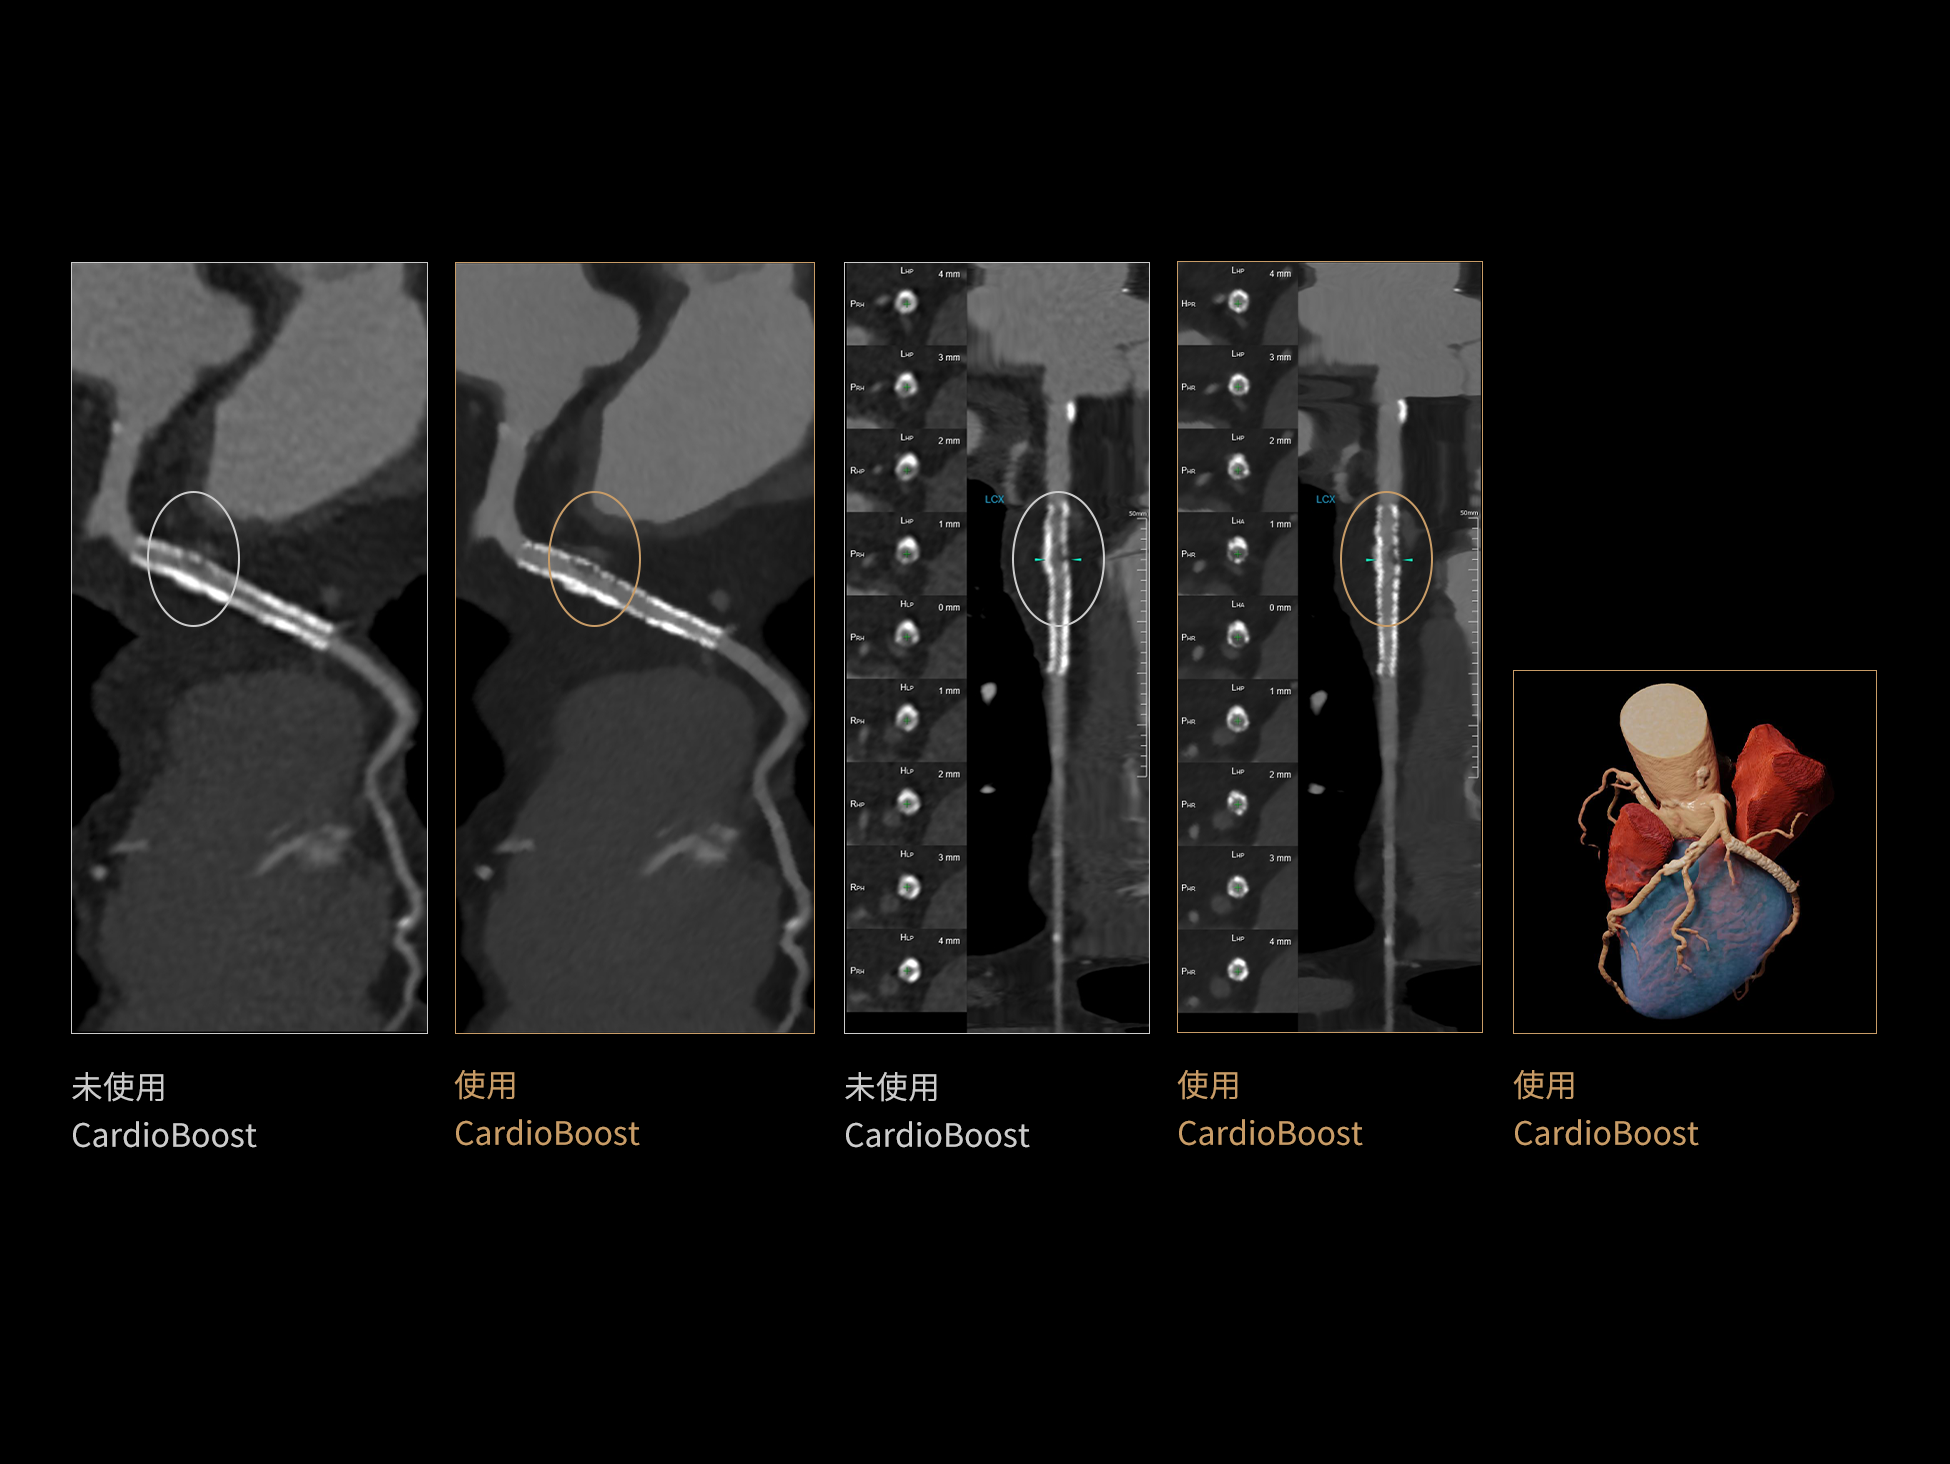

CardioBoost:专属网络设计,重塑心脏影像表现

目前心脏的 CT 检查还存在辐射剂量偏高、空间分辨率不足、 致密钙化伪影影响冠脉狭窄程度评估等方面的限 制[1][2]。CardioBoost 技术专为心脏 CT 高清成像而开发,通过 3D 神经网络的深度学习技术,利用先进的注意力机制在识别关键成像特征方面的出色表现,能够精确地聚焦于斑块、支架以及微小血管等关键细节,清晰展示这些结构与冠脉血管的边界,从而显著提高诊断的准确性,并提升医生的诊断信心。创新的 CardioBoost 心脏图像重建算法,不仅实现了图像清晰度的提升和伪影的去除,更能在减少辐射剂量的同时,保证心脏图像的高质量和图像纹理的自然。

采用 3D 神经网络的空间结构优势与精细的组织分类能力,CardioBoost 技术优化了组织对比,高清展示血管斑块,使斑块与血管边缘的轮廓清晰可辨,提升斑块诊断与评估的精确性。

借助 3D 神经网络设计、空间注意力机制聚焦与特征强化作用,CardioBoost技术提升图像的空间分辨率,实现冠脉支架的高清成像,对支架形态与管腔通畅度的评估更精准。

CardioBoost 整合先进的 3D 神经网络和空间注意力机制,大幅增强数据处理的速度与精确度。该技术能有效抑制由致密钙化引起的晕状伪影,清晰展现钙化斑块的原始结构和大小,对冠脉狭窄的评估更加精确可靠。